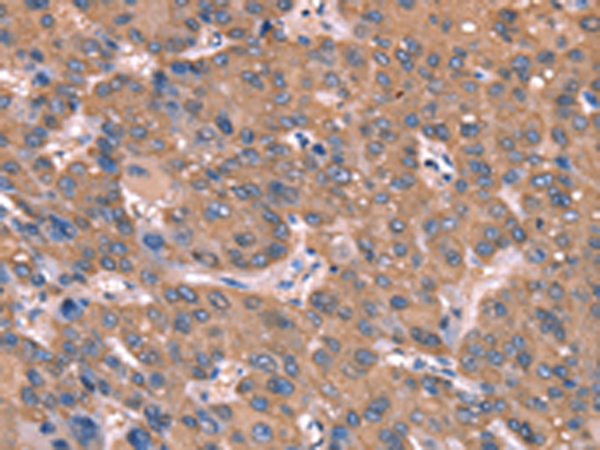

分类: 科研抗体货号: P04893别名:应用: WB,IHC反应种属: Human, Mouse